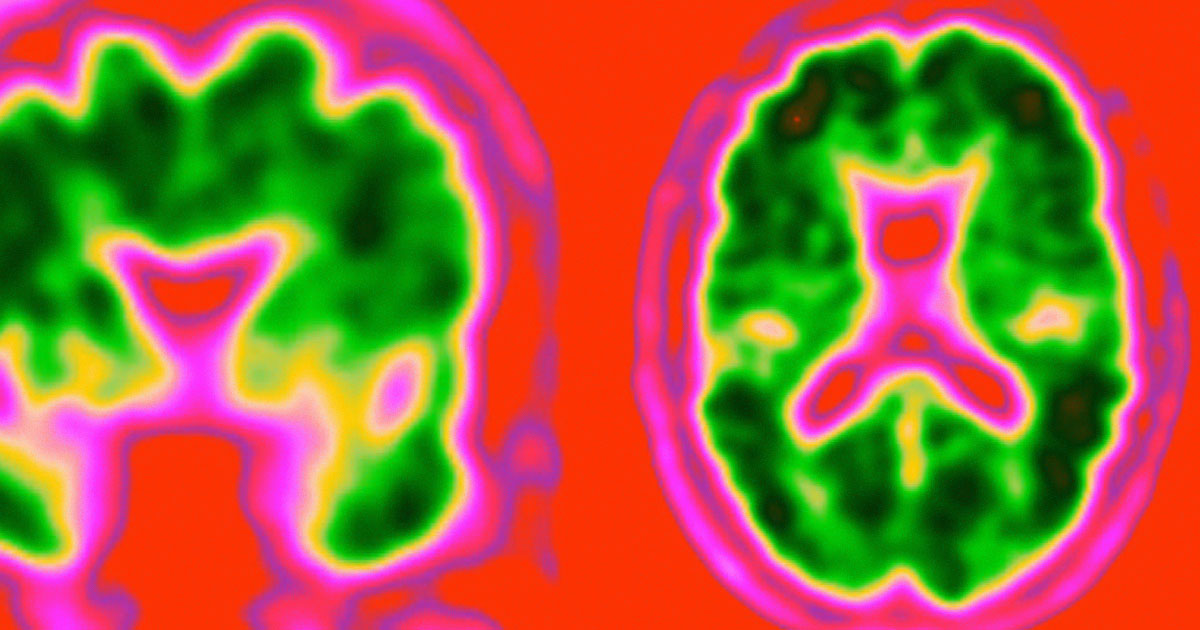

The blood test measures levels of amyloid beta, a protein that is found in the brains of Alzhheimer’s patients — a test that can currently be carried out only through an expensive PET scan.